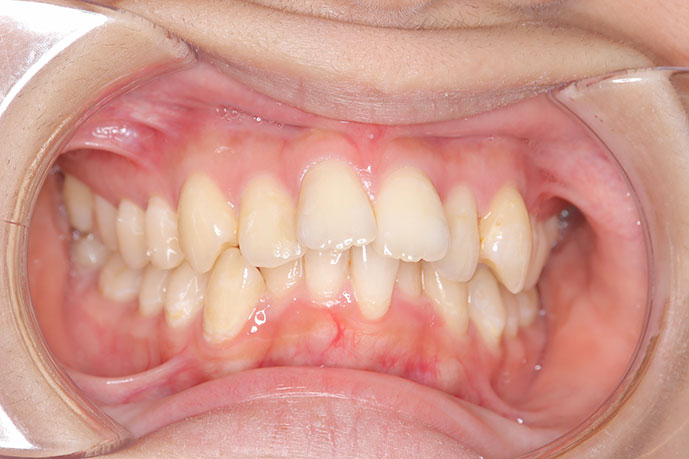

治療後